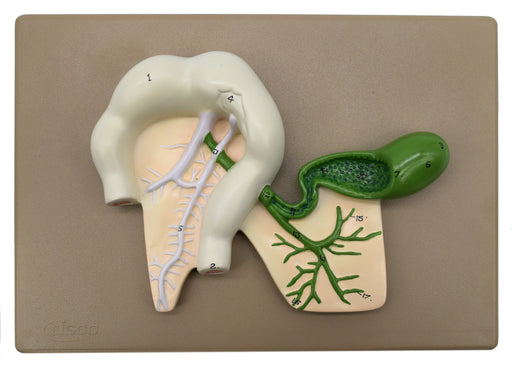

Human Pancreatic Duct Model, Three Dimensional, with Hand Painted Details - Mounted on Base, 10" x 7" - Eisco Labs

Model depicts human pancreatic duct. Mounted on a 10" X 7" base . Entire model stands 2.25" tall. Numbered with English Key Card. Hand painted Mod...

View full detailsAM0330 -